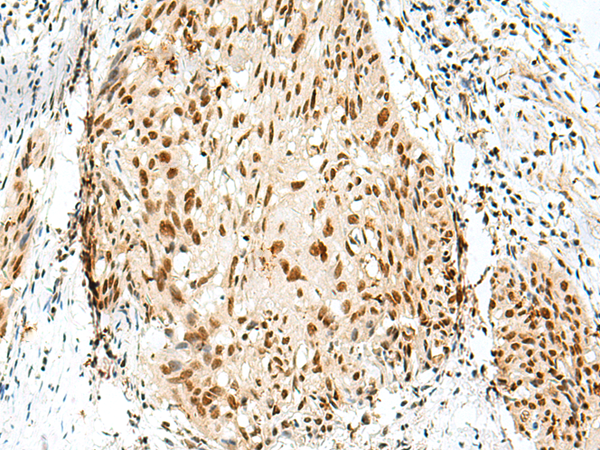

ELISA, IHC |

IHC positive control: |

Human esophagus cancer and Human tonsil |

IHC Recommend dilution: |

30-150 |